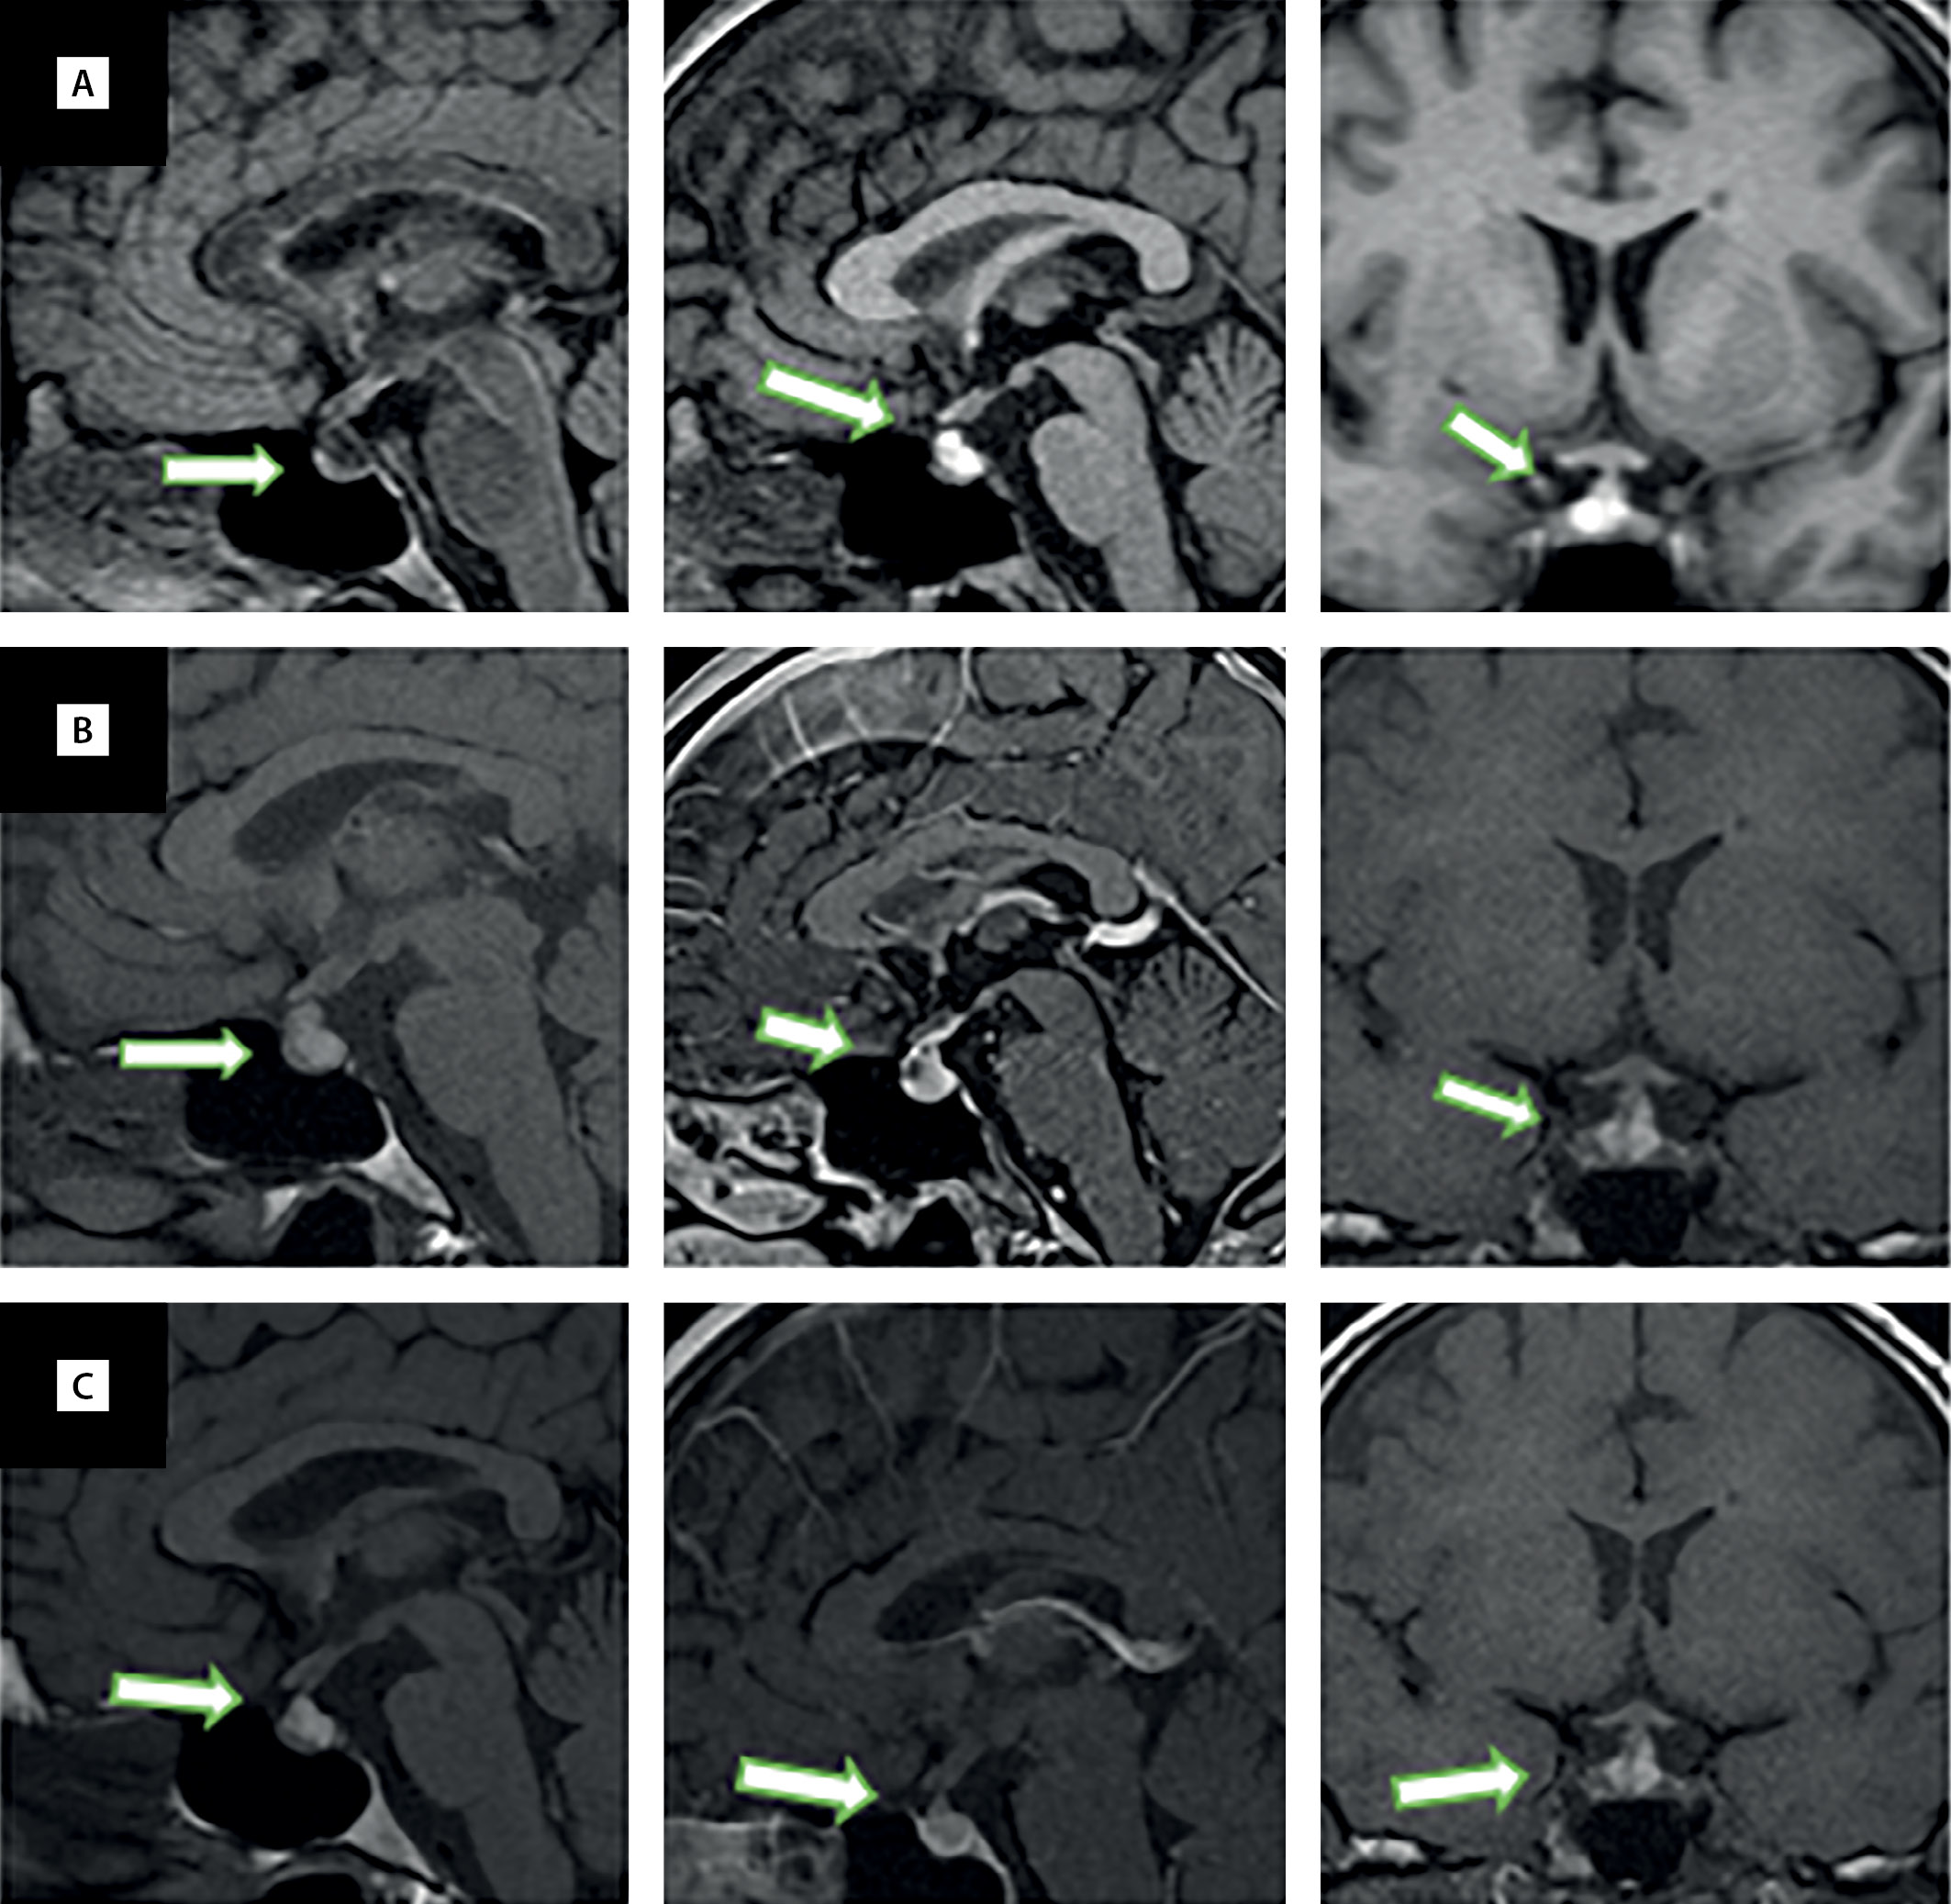

Рисунок 1. МРТ гипофиза в динамике.

Т1-взвешенные изображения до введения контраста, сагиттальный срез (левая колонка), Т1-взвешенные изображения после введения контраста, сагиттальный срез (средняя колонка), Т1-взвешенные изображения после введения контраста, фронтальный срез (правая колонка). А — август 2020 г.: впервые выявленная киста кармана Ратке. В — январь 2021 г.: увеличение кисты кармана Ратке, утолщение воронки гипофиза. С — апрель 2021 г.: уменьшение кисты кармана Ратке, отсутствие утолщения воронки гипофиза.

С 2018 г. пациентку беспокоят головные боли — при МРТ головного мозга заподозрили рассеянный склероз. Наблюдается у невропатолога, лечение не назначали. Регулярно выполняла МРТ головного мозга из-за предполагаемого рассеянного склероза, и в августе 2020 г. при очередном исследовании обнаружили кисту кармана Ратке (рис. 1).

Лечение было назначено спустя месяц от появления первых признаков гипопитуитаризма — пациентка получала заместительную терапию гидрокортизоном 20 мг в сутки, левотироксином 50 мкг ежедневно натощак и каберголином 1 мг в неделю. Через несколько недель от начала приема гидрокортизона отметила появление избыточной энергии, повышенной активности, в связи с этим самостоятельно снизила дневную дозу гидрокортизона до 5 мг, иногда вовсе пропускала дневную зону (принимала на 10 мг гидрокортизона утром). Самостоятельно отменила прием левотироксина в апреле 2021 г., длительность терапии составила 2 мес. Приведенные данные лабораторных анализов от апреля 2021 г. — на фоне отмены левотироксина, в дальнейшем данный препарат не принимала. На МРТ через 2 мес после перенесенной коронавирусной инфекции обнаружены увеличение ранее выявленной кисты кармана Ратке, а также утолщение воронки гипофиза, признаки инфундибулогипофизита (см. рис. 1).

Таким образом, на МРТ головного мозга через 5 мес после перенесенной коронавирусной инфекции обнаружили уменьшение размеров кисты кармана Ратке, отсутствие утолщения воронки, в целом — положительная динамика по сравнению с предыдущим исследованием (см. рис. 1). Также имеются убедительные доказательства частичного восстановления функций гипофиза после пангипопитуитаризма, развившегося в период реконвалесценции COVID-19-инфекции.